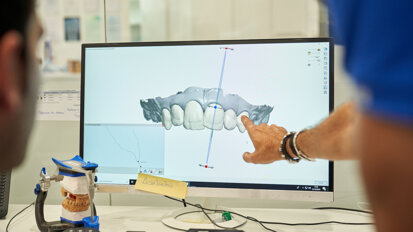

Na podstawie badania TK stwierdzono zachowanie stosunkowo dużej ilości tkanki kostnej, zarówno w wymiarze pionowy, jak i poziomym. Struktura kości charakteryzowała się dużą zawartością warstwy gąbczastej (słabo wysyconej w TK), a także bardzo ograniczoną warstwą kortykalną kości. W związku z tym zaplanowano wszczepienie większej liczby implantów niż w standardowym postępowaniu. Wykonany został szablon chirurgiczny z poziomu tkanek miękkich na podstawie badania TK. Wszczepienie implantów rozłożone zostało na 2 etapy, spowodowane ekstrakcją zębów 16 i 13.

W pierwszym etapie wszczepionych zostało 7 implantów, które zamknięto śrubami zamykającymi, pozostawiając je pod płatem śluzówkowo-okostnowym. Po zabiegu pacjentka zaopatrzona została w protezę akrylową osiadającą. Po 2 miesiącach doszczepione zostały pozostałe 3 implanty w okolicach 16, 15, 13, które również zostały pozostawione pod płatem śluzówkowo-okostnowym. Po kolejnych 4 miesiącach odsłonięto implanty i wykonano tymczasowy cementowany most akrylowy, który pacjentka użytkowała do czasu prawidłowego zagojenia się tkanek.